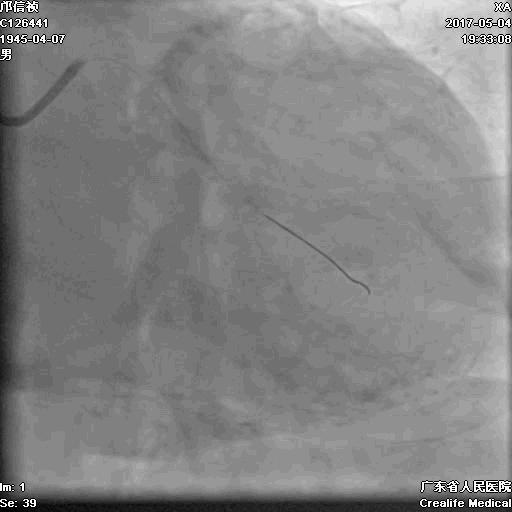

第三步:1月后

介入策略

-

尝试正向?

直接逆向?

逆向通道:1. LCX---PL?

2.LAD---PDA?

正向浅尝,改为逆向,LCX-PL

RRA:6F AL0.75 GC –RCA;

RFA:7F XB 3.5 GC—LCA 150cmcorsair

正向130cmFinecross微导管支持下尝试送PILOT150、Gaia 2导丝无法通过RCA闭塞段

SION导丝通过侧枝

逆向导丝:更换Gaia2

正向导丝:Gaia2,PILT150

正向导丝knuckle

2.5*15mm球囊扩张,逆向导丝尝试,但未能进入正向GC

1.正向2.5*15mm球囊扩张,Reverse CART

2.Guidezilla延长导管辅助下,逆向导丝进入正向GC

1.更换RG3导丝

2.GC送入普通导丝,保护LM